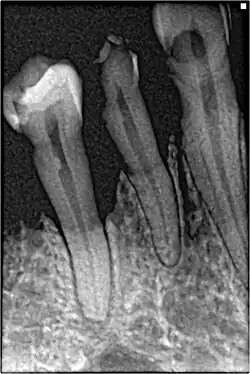

Periodontal recession on maxillary central incisors

Bone loss in periapical radiograph

The 2018 Disease Classification of Periodontal Diseases and Conditions breaks down the category of periodontitis into three forms and each of these forms are further broken down into two or more subcategories.[7]